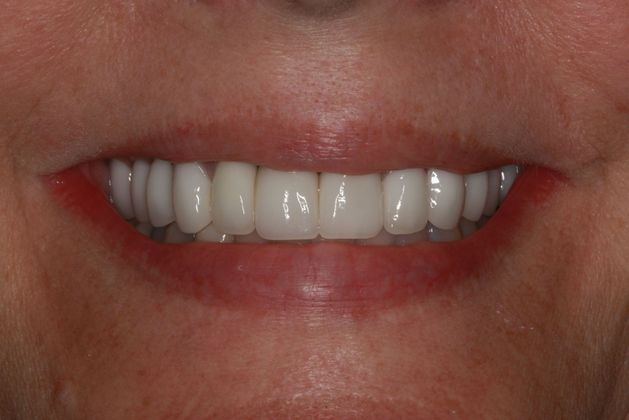

While the health benefits of restorative dentistry are clear, patients can also enjoy a higher level of self-esteem after receiving treatment. By addressing missing or damaged teeth, many patients achieve a healthier-looking smile that makes them feel more confident.

I am so pleased with my implants. Dr. Collier is excellent and has great bedside manner. His staff and his assistants are awesome. He wanted everything to be perfect even if that meant having an extra visit. I was very impressed with his credentials when I was doing my research for an implant specialist and I’m glad that I chose Southern Dental Implant Center.

View On GoogleHave been going to Dr. Collier for 10 years. He really cares . I had an emergency problem, and even though he was booked for the day, he made sure to work me into the schedule. I’ve had quite a bit of restorative dentistry in past 10 years, and couldn’t be happier with the outcome Dr . Collier is a perfectionist when it comes to making things look great. He has always made sure that I was 100% satisfied with the work he performed.

Here at Southern Dental Implant Center, we believe everyone deserves to have a healthy, functional smile. It is essential to get the dental care you need right away to avoid more significant problems down the road. By being proactive, patients can enjoy a more confident smile in just a few appointments and no longer have missing or damaged teeth negatively impact their life. To schedule your consultation, contact us online or call our Cordova, TN, office serving Memphis and the Mid-South area at: